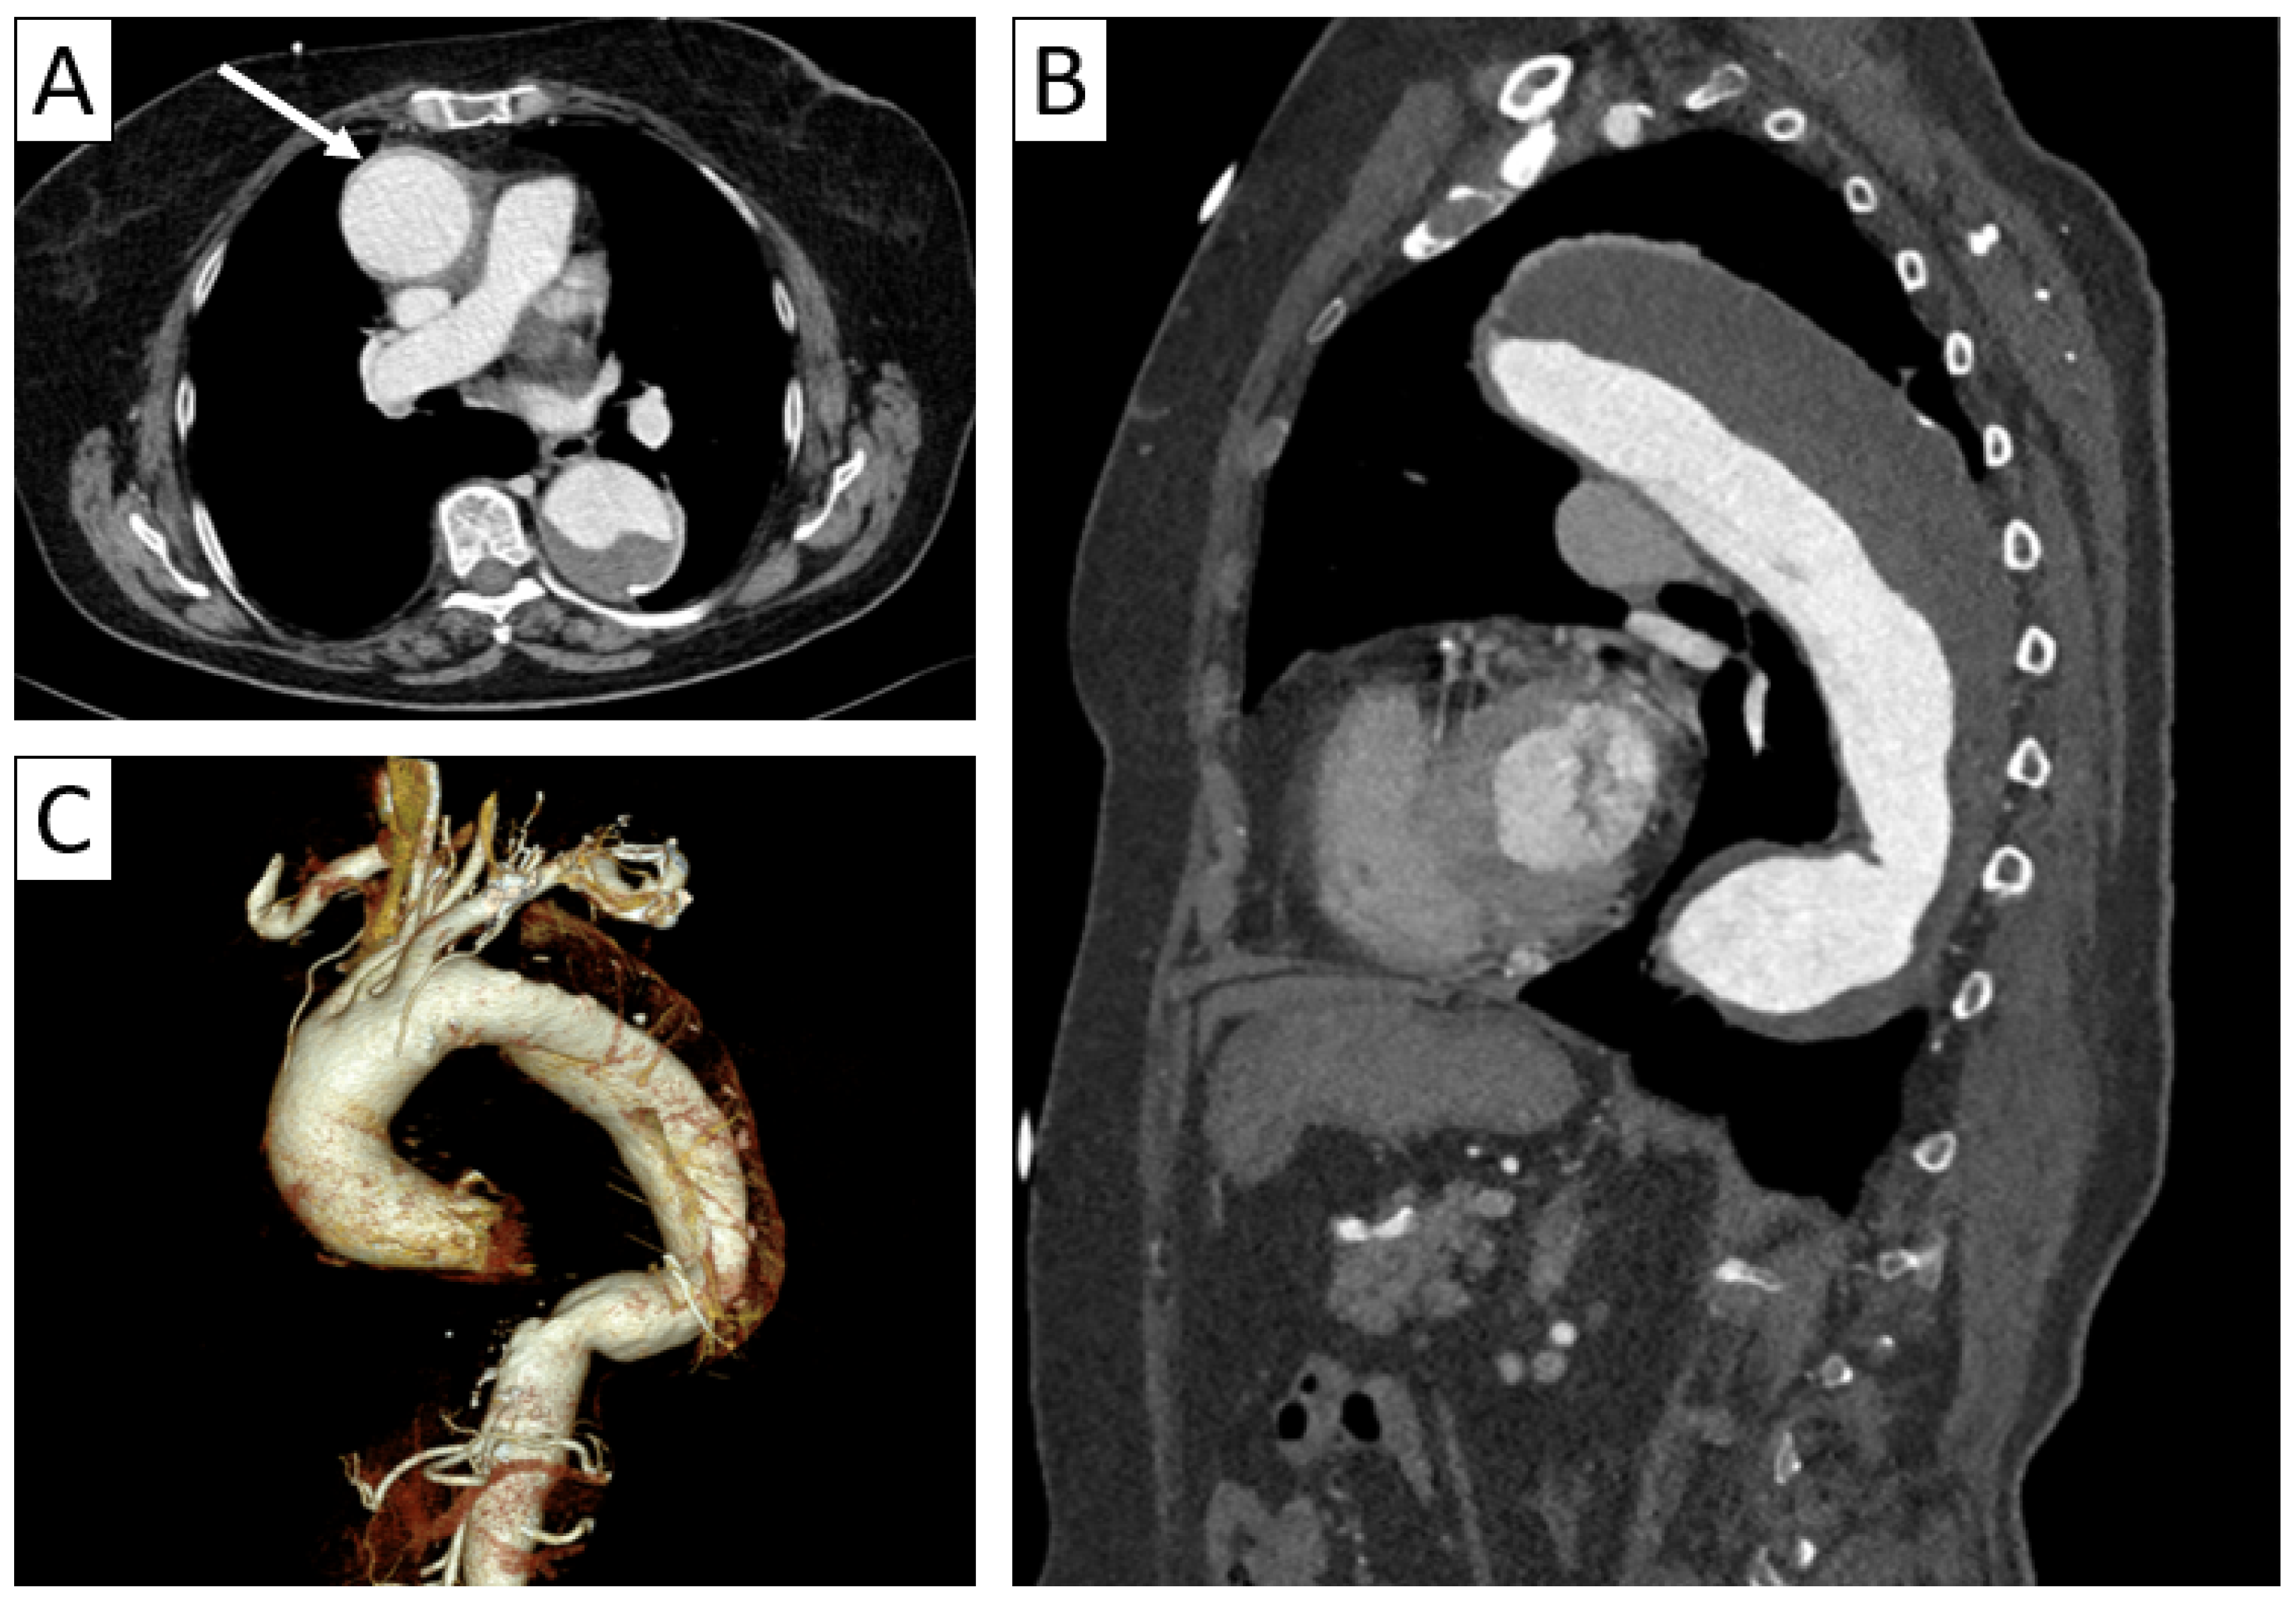

6.2. Imaging Findings in Primary LVV

6.2.1. Giant Cell Arteritis

| CTA | Circumferential parietal thickening Vessel wall enhancement | Circumferential parietal thickening Vessel wall enhancement Luminal stenosis or narrowing |